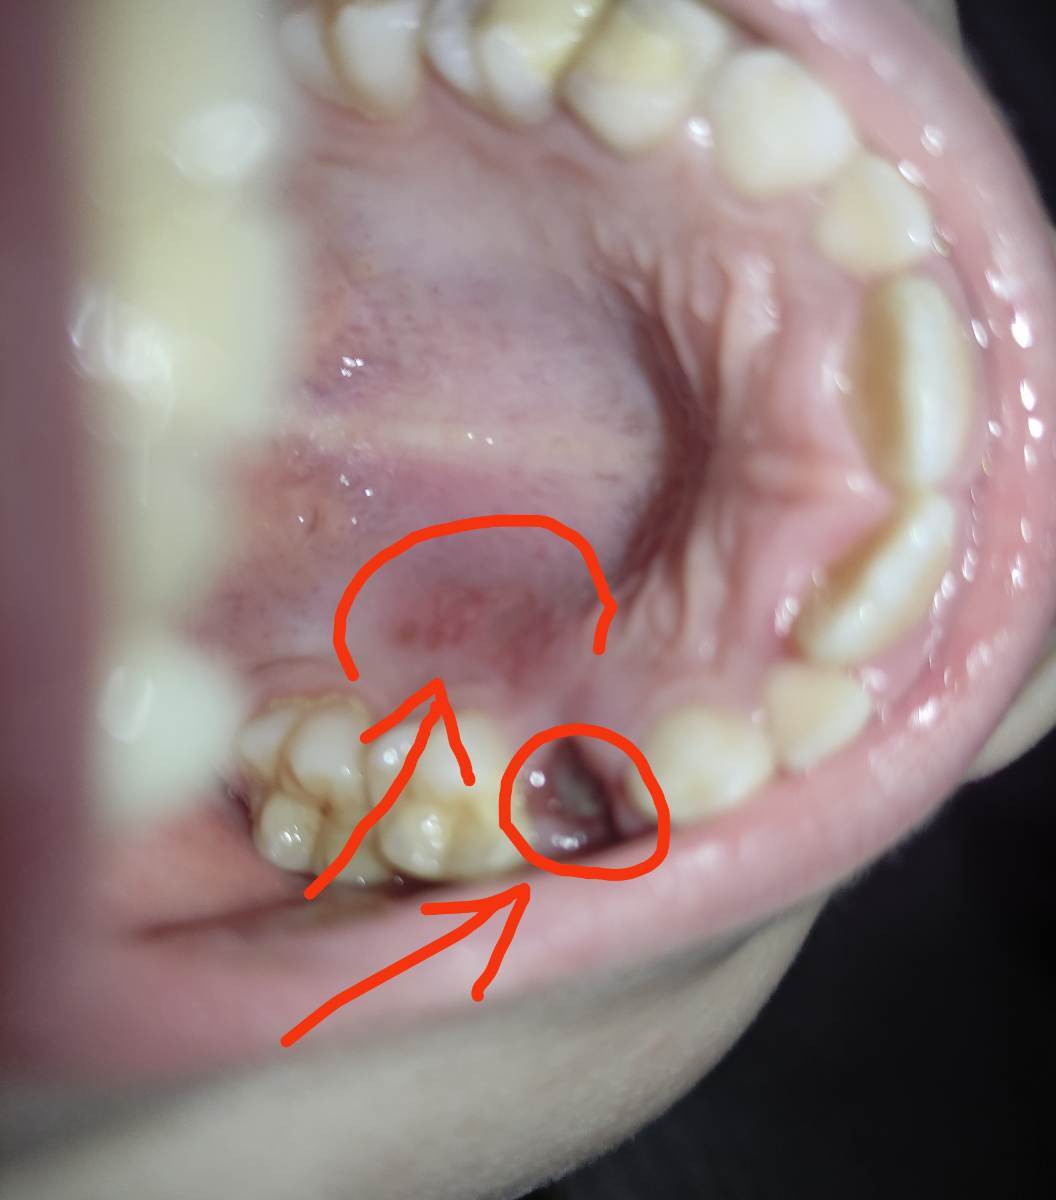

Здравствуйте, подскажите пожалуйста,что может быть после удаления молочного зуба.

Месяц назад лечили молочный зуб,ребёнок часто жаловался на то,что под пломбой чешется,а в выходные 4.04 зубик воспалился,пару дней обрабатывали холисалом,краснота ушла,но не до конца. 6.04 обратились в стоматологию,удалили,долго не останавливалась кровь.

Вчера и сегодня есть небольшая температура 37 и до сих пор не проходит краснота на дёснах,в дырке сгусток серого цвета, ребёнок не может описать ощущения,не понимает.

Подскажите,что это может быть?